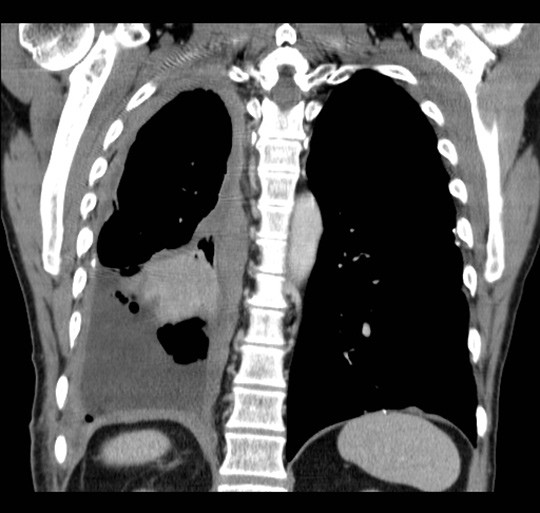

Typisk vekstmønster for malignt pleuralt mesoteliom

En mann i 60-årene ble utredet på bakgrunn av økende dyspné. Han hadde vært eksponert for asbest noen uker i 1970-årene, og hadde røykt fra 15 års alder. Det ble ikke funnet atypiske celler i pleuravæske. Diagnosen pleuralt mesoteliom ble fastsatt etter åpen pleurabiopsi. 18-fluorodeoksyglukose positronemisjonstomografi kombinert med computertomografi (18F-FDG PET/CT) ble rekvirert for å avklare om han kunne være kandidat for kirurgi.

18F-FDG tas opp i celler med høyt energibehov, som hjerte- og hjerneceller, betennelsesceller og maligne celler. Avbildning med PET/CT viser til venstre opptak i et malignt pleuralt mesoteliom med typisk utbredelse langs mesotelkledde hinner, her langs høyre pleura, inkludert lappespaltene. Til høyre viser CT alene de strukturelle forandringene i detalj, men skiller dårligere mellom viabelt tumorvev og benigne forandringer, som atelektase.

18F-FDG PET/CT gir mulighet for mer nøyaktig bestemmelse av sykdomsutbredelsen enn CT alene. Dette utnyttes blant annet til å selektere pasienter med begrenset sykdom for kirurgi. Ved pleurafortykkelse av ukjent årsak kan undersøkelsen være til hjelp i vurderingen av hvorvidt fortykkelsen skyldes malignitet. På grunn av lav oppløselighet har undersøkelsen imidlertid begrenset sensitivitet for små eller tynne maligne lesjoner (< 5 – 8 mm, avhengig av kamerateknologi). Tynne eller små maligne lesjoner i pleura inkludert i lappespalter kan derfor være PET-negative. Tykkere lesjoner uten opptak av 18F-FDG er mest sannsynlig benigne, selv om man må ta høyde for enkelte tumortyper som ikke tar opp stoffet.

Hos denne pasienten ble utbredelsen vurdert å være for omfattende til at kirurgi var aktuelt. Han ble behandlet med palliativ kjemoterapi med målsetting livsforlengelse og symptomkontroll.